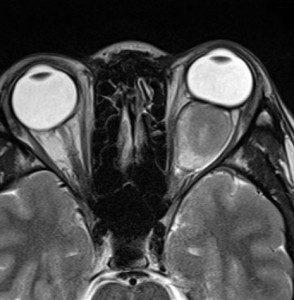

眼窩内に限局する視神経膠腫:神経鞘腫と鑑別が難しいもの

主訴は進行性の眼球突出です。視力低下は軽度で,視野欠損は左眼の下半分でした。入院前の画像では眼窩内神経鞘腫を疑う画像でした。

しかし,CISSの画像では中枢側の視神経との連続性があり,これではじめて視神経膠腫と診断できました。もちろん毛様細胞性星細胞腫です。眼球,眼球運動,眼瞼の動きを温存して腫瘍を眼球後極から切断して全摘出しました。